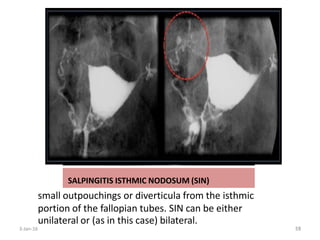

SALPINGITIS ISTHMICA NODOSA

(Diverticulosis of the fallopian tube)

• Irregular benign extensions of the tubal epithelium into the myosalpinx

mainly at the isthmic/proximal portion

• Out pouchings of isthmus

• Unilateral or bilateral

• Unknown cause

• Associated with infertility,

PID and ectopic pregnancy

SALPINGITIS ISTHMIC NODOSUM (SIN)

small outpouchings or diverticula from the isthmic

portion of the fallopian tubes. SIN can be either

unilateral or (as in this case) bilateral.